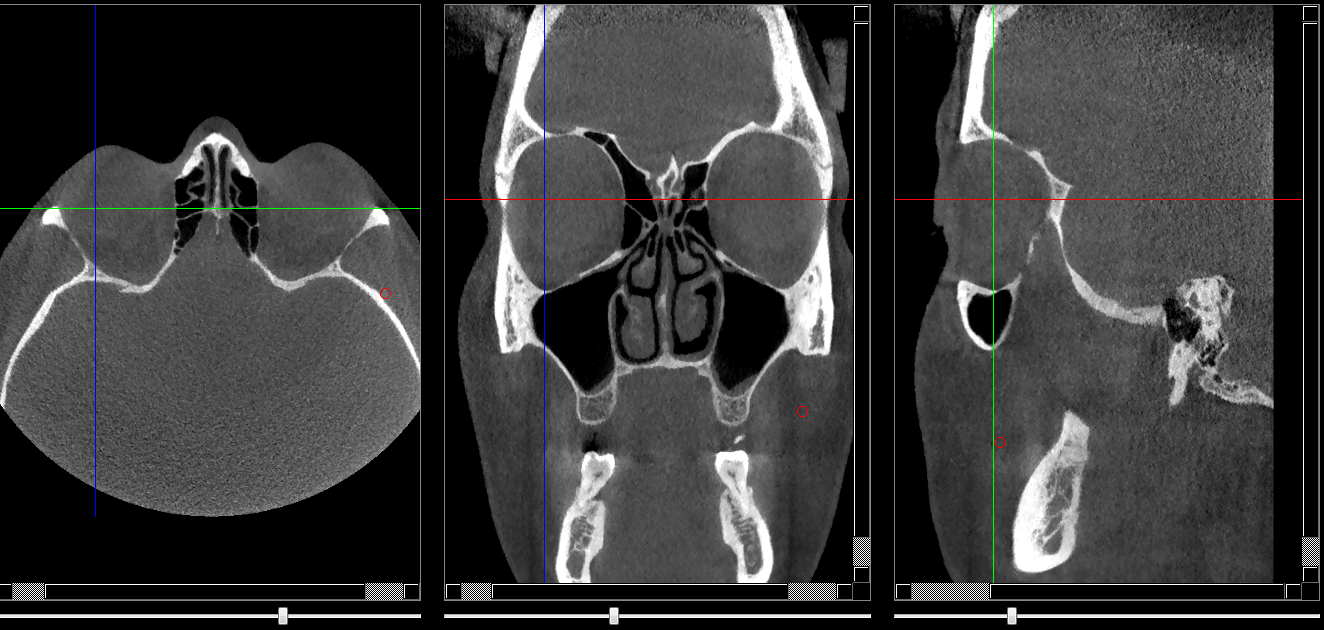

Repères anatomiques

- Coupe transversale

- Début : grande aile du sphénoide

- Fin : Base du crane

- Coupe frontale

- Début : Cornet nasal sup

- Fin : Début du sinus sphénoide

- Coupe saggitale

- Début : Processus frontal

- Fin : Cornet nasal

Infos sur l'image

- Auteur : Pr Bourzgui

- Co-auteur : Dr Makoure

- Affiliation : Orthopédie dento-faciale

- Date production : 2019